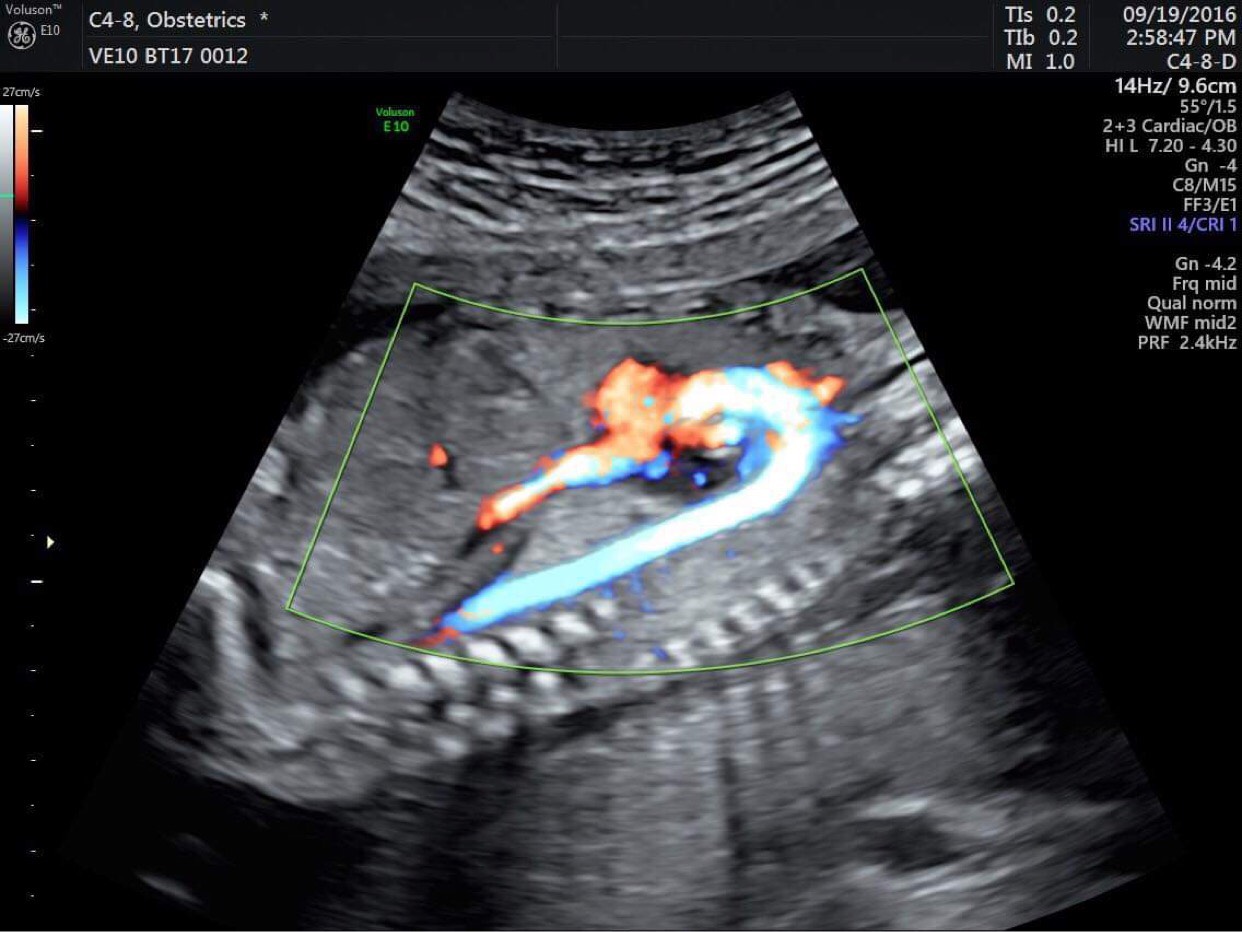

Có thể thấy rằng siêu âm thai nhi là một việc làm rất quan trọng, nó giúp chúng ta đánh giá được nhiều vấn đề liên quan đến thai nhi, giúp bố mẹ có thể nhìn thấy được sự lớn lên của bé yêu. Tại PKĐK Thuận Kiều, dịch vụ siêu âm thai nhi 2/3/4D, siêu âm Doppler màu tầm soát dị tật mạch máu ở tim và não của thai nhi… cùng đội ngũ bác sĩ chuyên khoa giỏi, sẽ giúp các mẹ có một thai kỳ an toàn, khỏe mạnh.